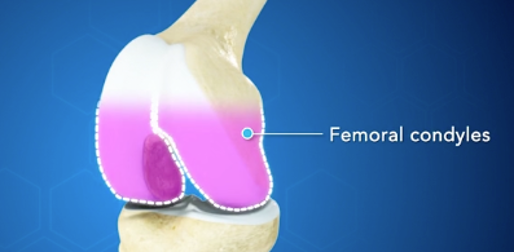

Condylus:

A két femorális condylus alkotja az ízesülő csontvégeket a combcsont térd felőli végén.

Ezeket porc borítja, mely a sima ízületi felszínt képez a csontokon így segíti a combcsont-sípcsont felső részének egymáson való könnyed elmozdulását.